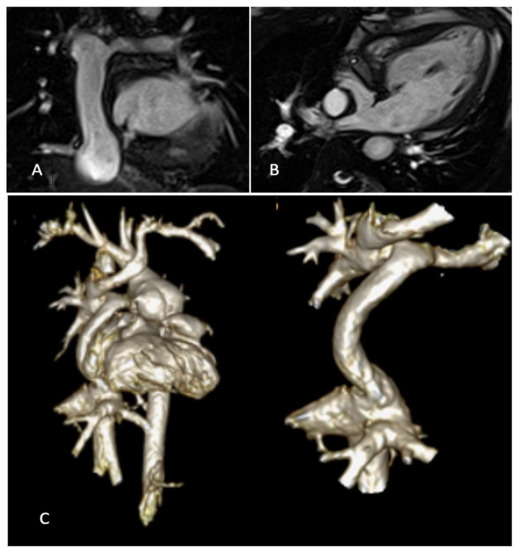

Ventricle function assessment by echocardiography is shown in Figure 1.

Figure 1. Ventricle function is assessed in a, b, c and d by AV S/D, 3D EF, LS, and FAC, respectively.